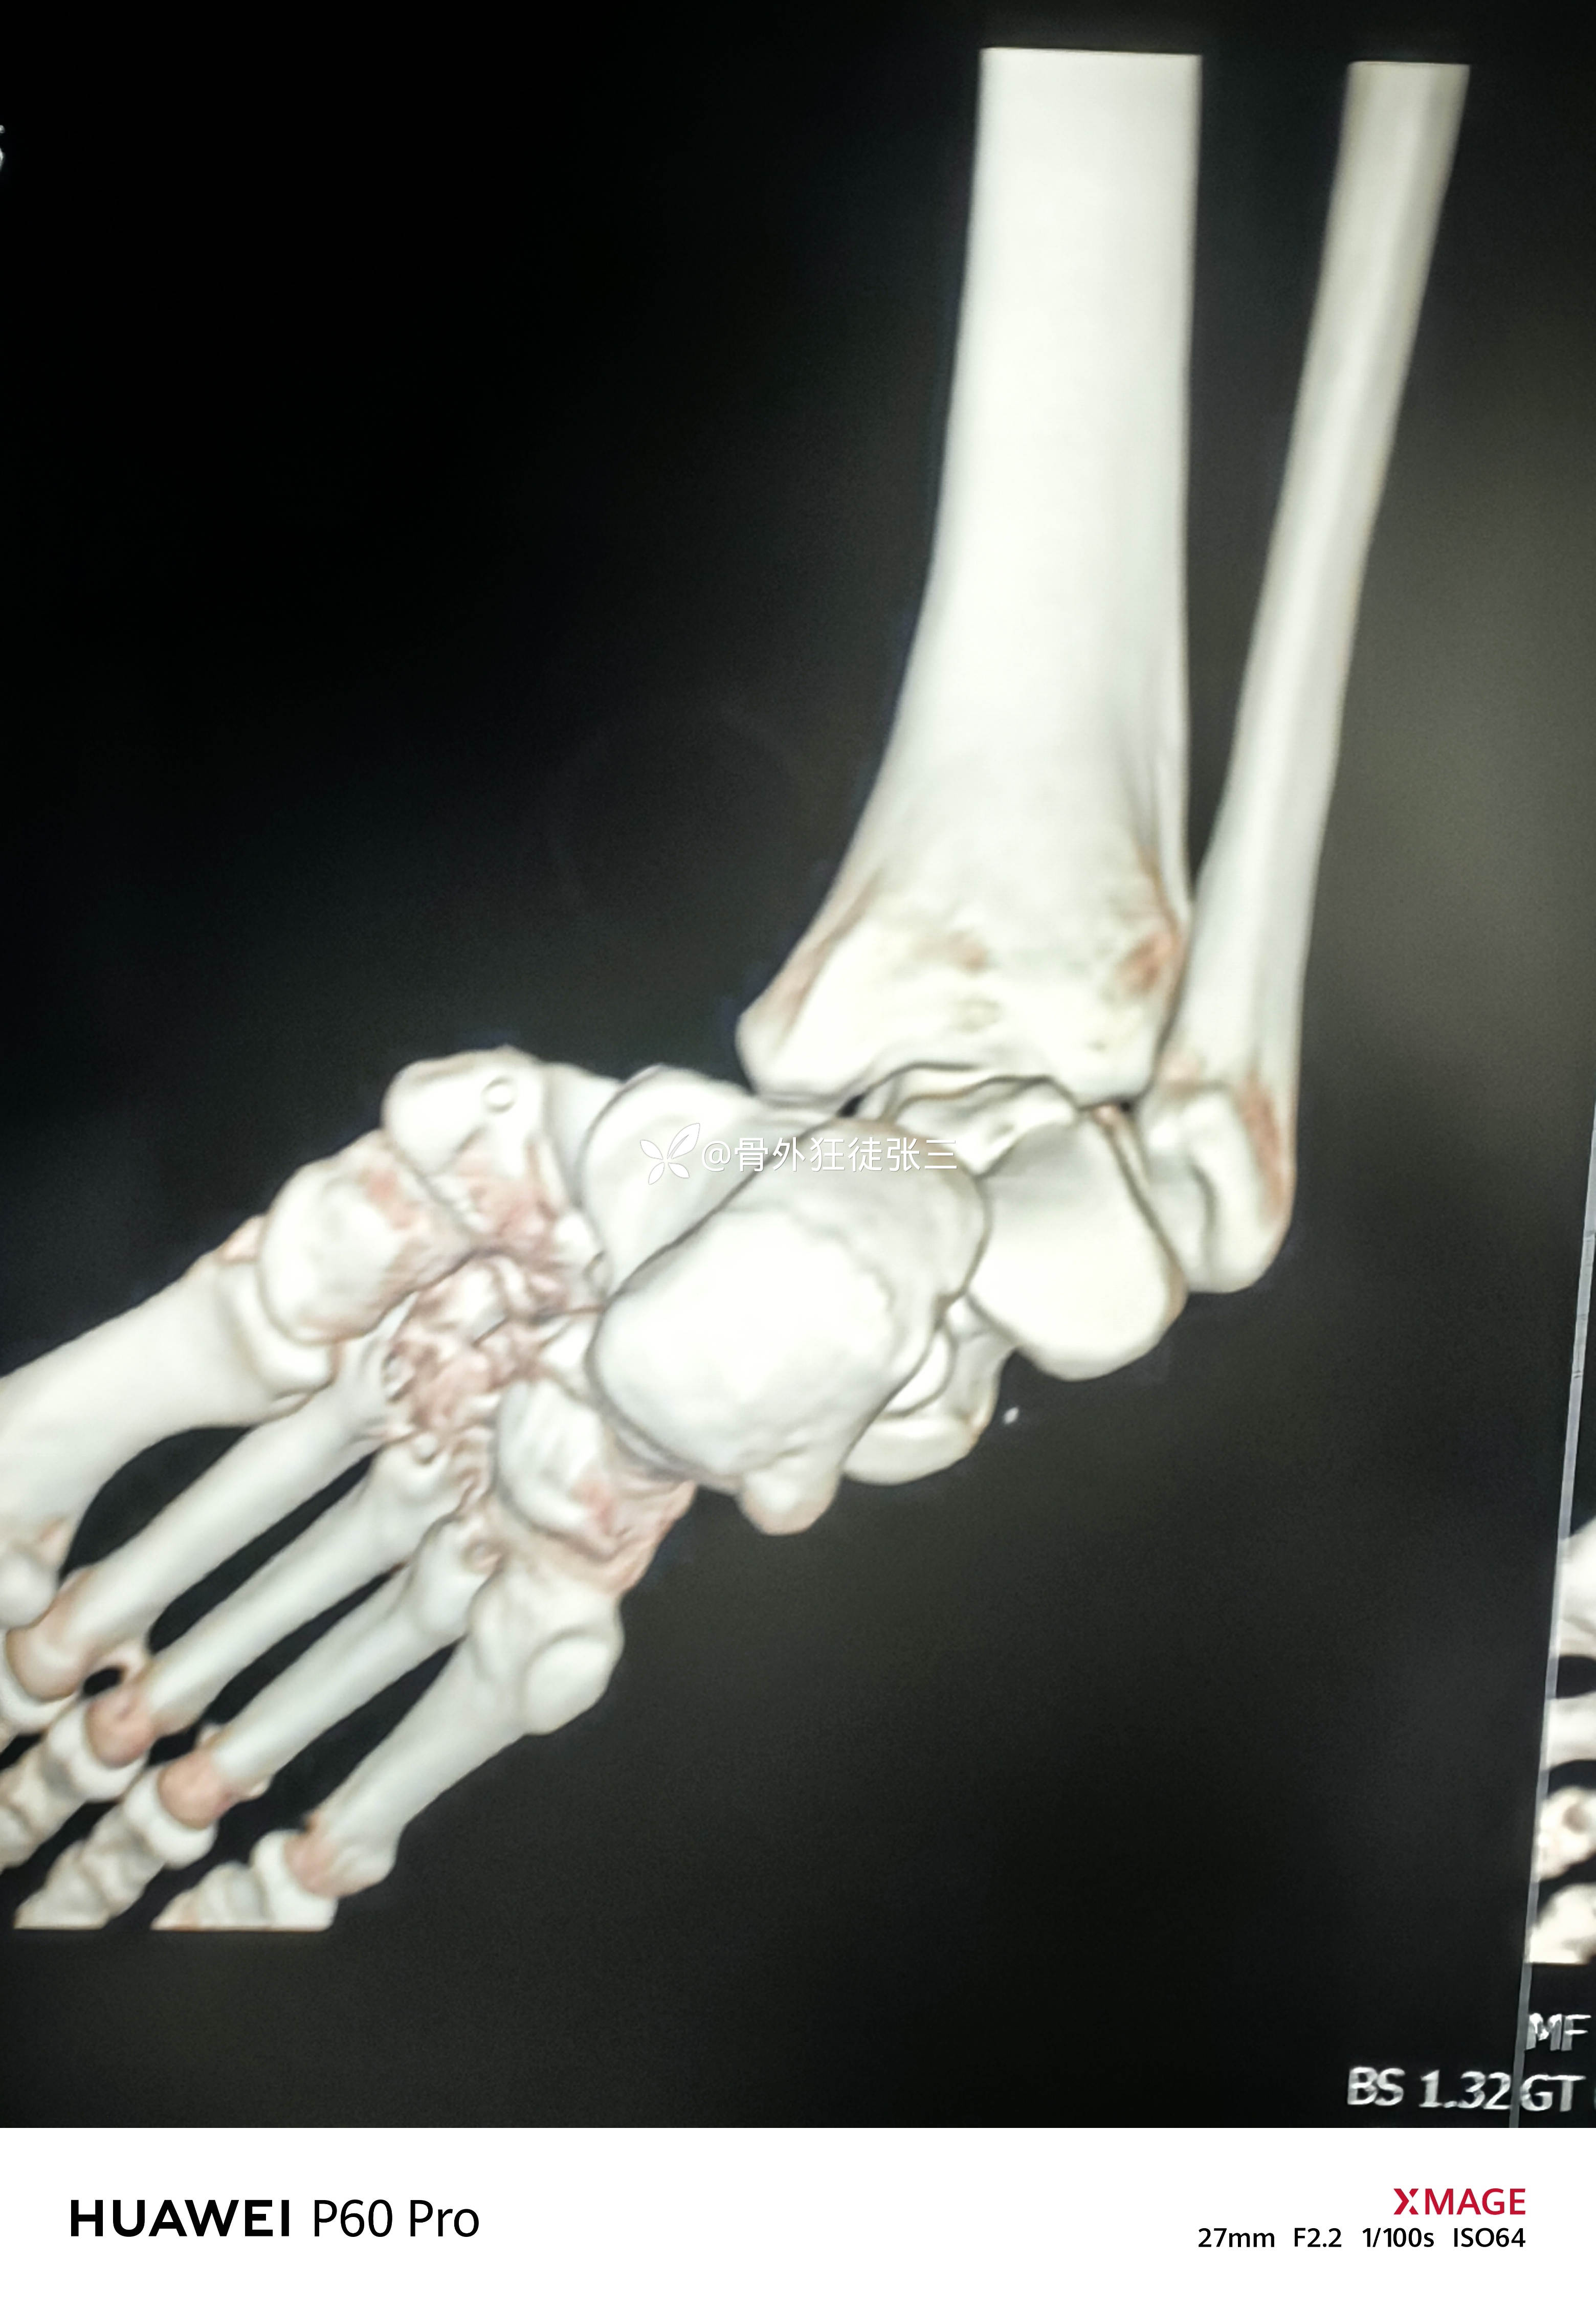

罕见损伤:距下关节脱位

主诉:车祸扭伤右踝关节致肿痛、畸形、活动受限1小时。

辅助检查:

右距下关节脱位(内侧型)